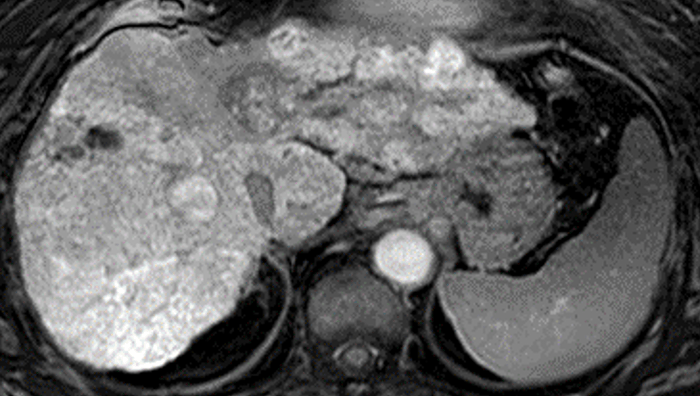

EOB-MRIは、肝がん診療には欠かせない、日常的に広く行われている検査の一つです。肝がん患者において、免疫チェックポイント阻害剤療法の直前に撮影されたEOB-MRIの画像とその後の病状の経過を調べたところ、画像中に背景の肝臓と比べて同等または少し白く映ったしこり(結節)は、免疫チェックポイント阻害剤療法の効果が少なく、増大する速度が速いことが示されました。

本研究は、Wnt/β-カテニンシグナル※3 の活性化状態が、EOB-MRIの肝細胞相※4 において、背景の肝臓より信号強度が高いか等しい結節(等~高信号結節)として現れるという仮説に基づき、切除不能肝がんに対する免疫チェックポイント阻害剤の治療抵抗性を予測することを目的として行われました。免疫チェックポイント阻害剤単独療法の直前にEOB-MRIを撮影していた18症例68結節を対象としており、その内訳は、背景の肝臓より信号強度が高いか等しい結節(等~高信号結節)が23個、背景の肝臓より信号強度が低い結節(低信号結節)が45個でした。

これらの症例について、EOB-MRIの肝細胞相を調べたところ、等~高信号結節を有する患者では、治療効果があった患者の割合(ORR)は12.5%、病勢コントロール率(DCR)は37.5%でした。一方、低信号結節のみを有する患者では、治療効果があった患者の割合は30.0%、病勢コントロール率(DCR)は70.0%でした。また、無増悪生存期間中央値※5(PFS中央値)は、等~高信号結節の患者で2.7カ月、低信号結節の患者で5.8カ月。各結節が20%以上増大するまでの時間の中央値は、等~高信号結節では1.97カ月、低信号結節では未達(半数以上の結節で増大を示さない結果)でした。

これによって、EOB-MRIの肝細胞相で等~高信号を示した結節は、低信号を示した肝がんと比較して、免疫チェックポイント阻害剤単独療法の効果が有意に劣ることが明らかになりました。また、等~高信号結節は免疫チェックポイント阻害剤の治療中により早く増大し、腫瘍が再発あるいは進行するまでの期間が有意に短くなることも示されました。これらの結果は当初の仮説を裏付けるものであり、EOB-MRIの肝細胞相において、等~高信号の結節が免疫チェックポイント阻害剤単独療法の反応性低下を予測するバイオマーカーになり得るということを強く支持するものでした。

※3 Wnt/β-カテニンシグナル:Wnt/β-カテニンは、肝細胞がんや他のがんで検出される細胞増殖能が増強する遺伝子変異の一つ。遺伝子が活性化することで腫瘍を取り巻く環境では様々な情報伝達が起こるが、この遺伝子が活性化することにより、OATP1B3という輸送体が増えるため、EOB-MRIで用いられる造影剤が腫瘍内に取り込まれて高信号結節(白い結節)として認識できる。この遺伝子変異はがん細胞に対する免疫機能を低下させる役割も持っており、一般的に免疫チェックポイント阻害剤が効きにくいといわれている。

※4 肝細胞相:肝特異的造影剤「EOB/プリモビストR(ガドキセト酸ナトリウム)」を投与し、20~40分ほど経過してから撮像するT1強調画像。肝細胞がんでは、一般的にOATP1B3という輸送体の発現が低下するため、細胞内への造影剤の取り込みが低下し、低信号の結節として描出される。一方、OATP1B3の発現が増えると、細胞内へ造影剤の取り込みが亢進して、高信号の結節として描出される。